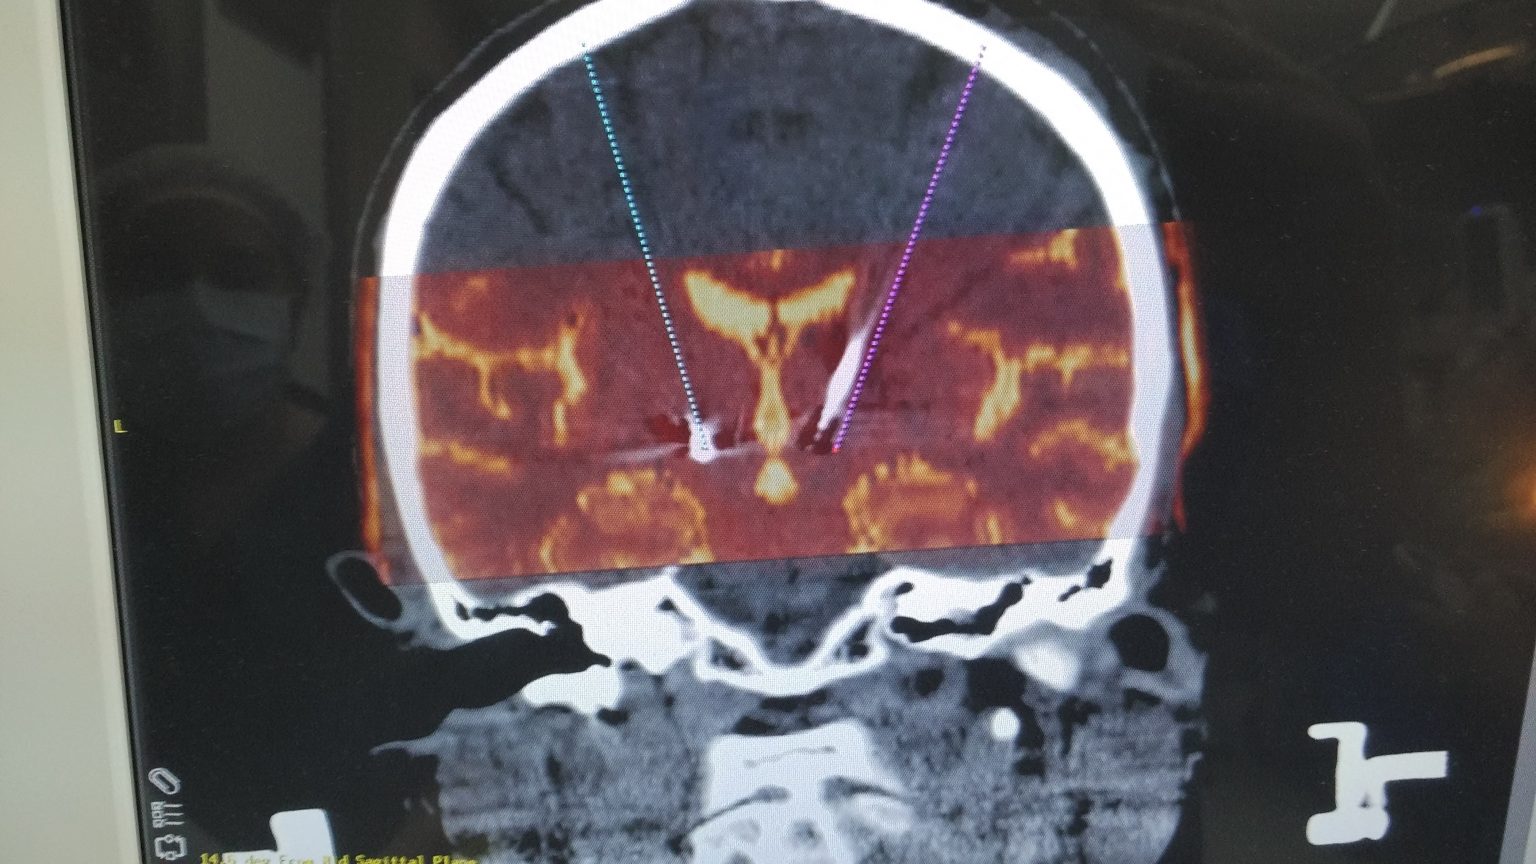

Understanding the Process of Deep Brain Stimulation (DBS) Surgery

Deep brain stimulation surgery Stock Image C036/0668 Science Deep Brain Stimulation Surgery Side Effects Choosing deep brain stimulation surgery. It’s also important to consider the complications and side effects of medications you take since their dosages can often be reduced following surgery. What is deep brain stimulation and how does it work? What is the surgical process for implanting deep brain electrodes? Dbs surgery is not recommended for all people living with parkinson’s disease. Deep Brain Stimulation Surgery Side Effects.